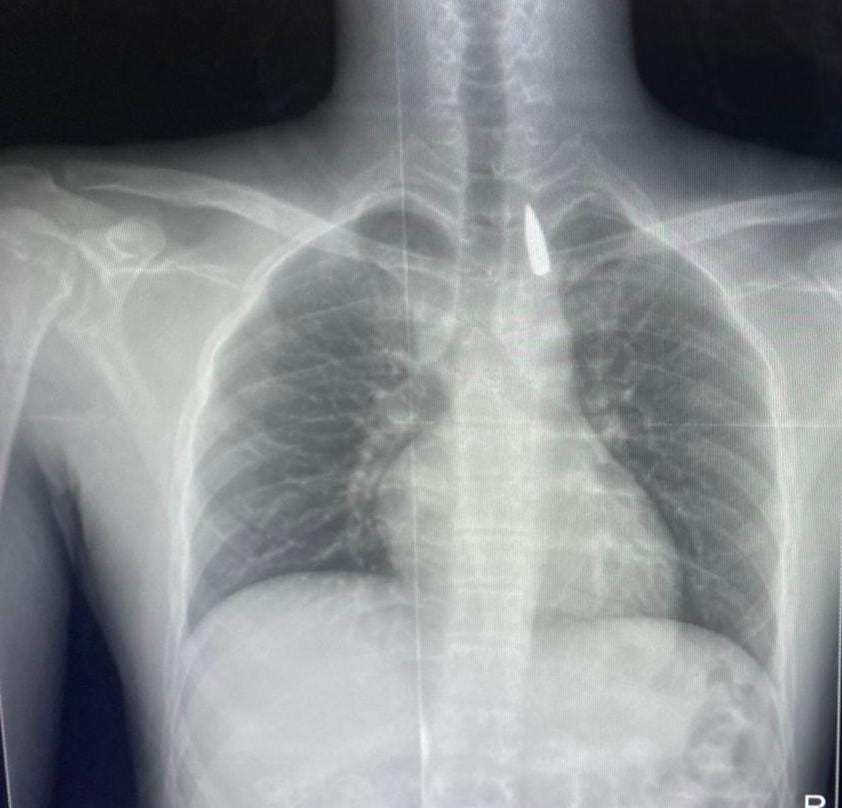

وأوضح الدكتور تامر عبد الله، عميد كلية الطب ورئيس مجلس إدارة المستشفيات الجامعية، أنه في يوم 21 أكتوبر 2025، تمكن فريق من أطباء قسم جراحة القلب والصدر والتخدير والمعاونين من إجراء جراحة دقيقة بالغة الخطورة لأحد المرضى المحجوزين من قطاع غزة، والذي كان قد تعرض لإصابة بطلق ناري في الرأس منذ فترة، استقر المقذوف على إثرها داخل تجويف القفص الصدري قرب الشريان الأورطي، وهو أكبر وأهم شرايين الجسم والمسؤول عن تغذية جميع الأعضاء الحيوية، وأضاف أن الفريق الطبي، رغم دقة الحالة وتعقيدها، نجح في استخراج المقذوف بأمان بعد عملية جراحية نادرة استمرت عدة ساعات داخل المستشفى الجامعي الجديد، حيث خضع المريض بعدها للرعاية الطبية اللازمة، وحالته حاليًا مستقرة وتحت المتابعة الدقيقة من الفريق المختص.